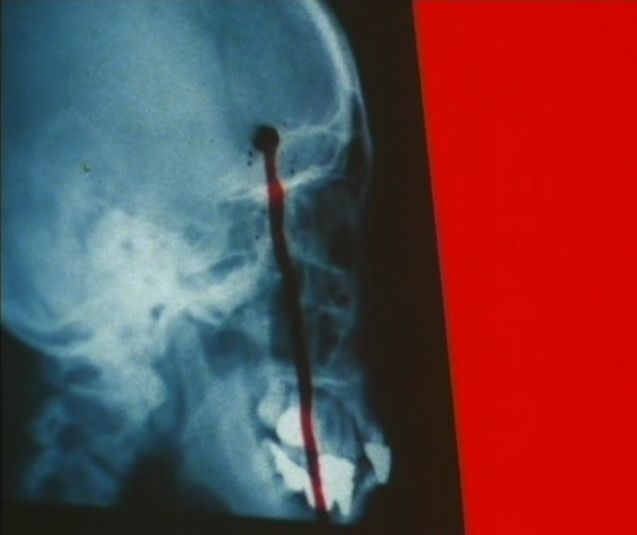

Ana no Kiba (1979)

Directed by: Seijun Suzuki